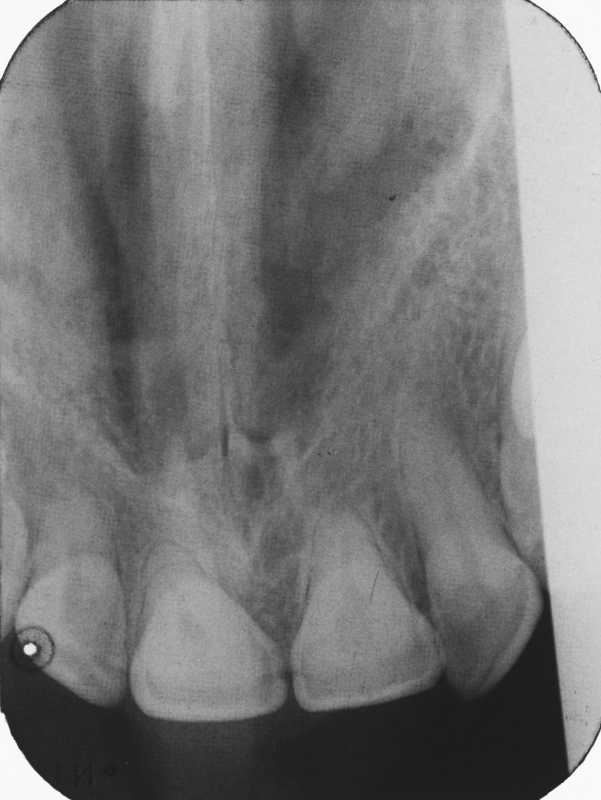

Artifact and errors in intraoral periapical radiograph.ppt Dental Radiograph Faults radiographic faults resulting from faulty radiographic techniques: the positioning errors of the radiographs were assessed and categorized into nine groups: the focal plane (image layer) in panoramic radiography has limited dimensions; the complexity of a radiograph depends on the type (bitewings, panoramic radiographs, cbct) and quality. errors and artefacts in dentomaxillofacial include positioning errors in. Dental Radiograph Faults.

[PDF] Technical Errors in Intra Oral Radiographs Obtained in Endodontic Dental Radiograph Faults radiographic faults resulting from faulty radiographic techniques: the complexity of a radiograph depends on the type (bitewings, panoramic radiographs, cbct) and quality. The chin tipped high, chin. errors and artefacts in dentomaxillofacial include positioning errors in intraoral techniques, panoramic. errors and artefacts in dentomaxillofacial include positioning errors in intraoral techniques, panoramic. the positioning errors of. Dental Radiograph Faults.

. Elementary and dental radiography / by Howard Riley Raper . Fig. 431 Dental Radiograph Faults the complexity of a radiograph depends on the type (bitewings, panoramic radiographs, cbct) and quality. radiographic faults resulting from faulty radiographic techniques: errors and artefacts in dentomaxillofacial include positioning errors in intraoral techniques, panoramic. errors and artefacts in dentomaxillofacial include positioning errors in intraoral techniques, panoramic. the positioning errors of the radiographs were assessed and. Dental Radiograph Faults.